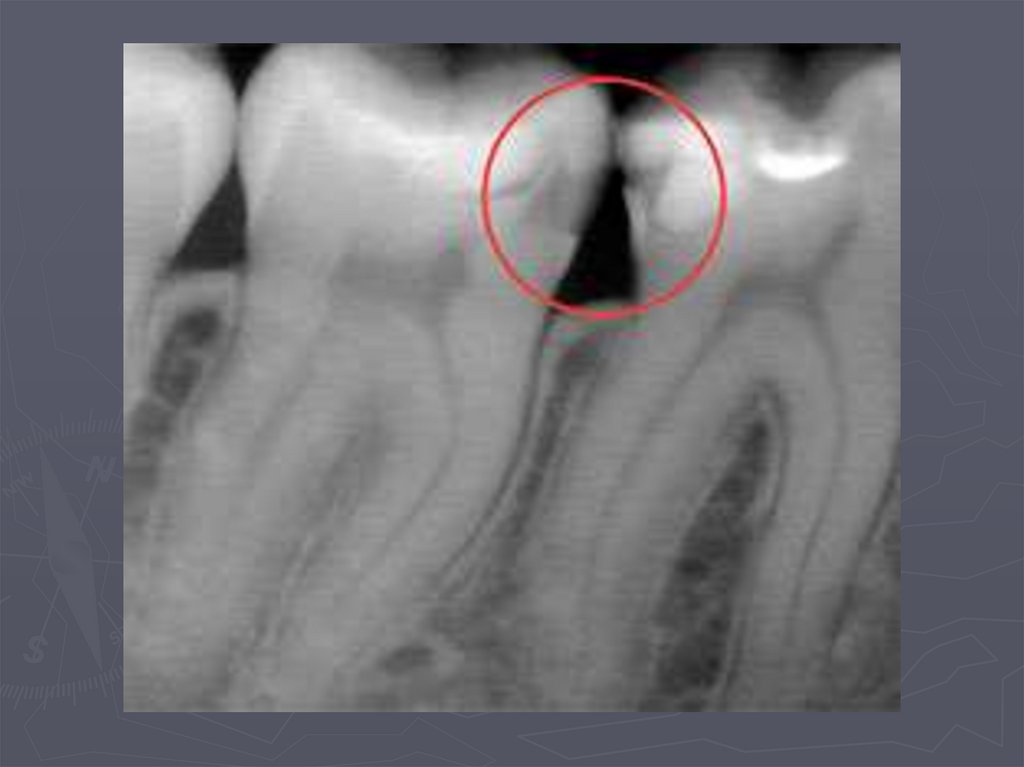

РЕНТГЕНОЛОГИЧЕСКИЙ МЕТОД –

применяется:

в случаях крайнего затруднения

диагностики,

► при локализации полостей на

апроксимальных поверхностях,

► при тесном положении зубов.

93. Кариес на рентгеновских снимках